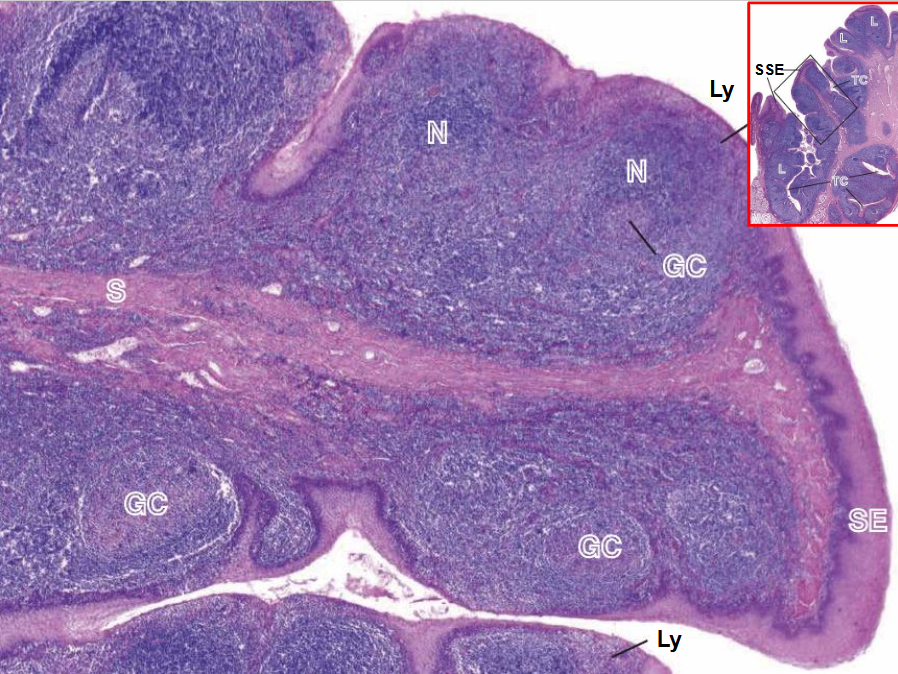

Amígdala de humano

N - Nódulo linfático

S - submucosa

CG - centro germinativo

Ly - linfocitos